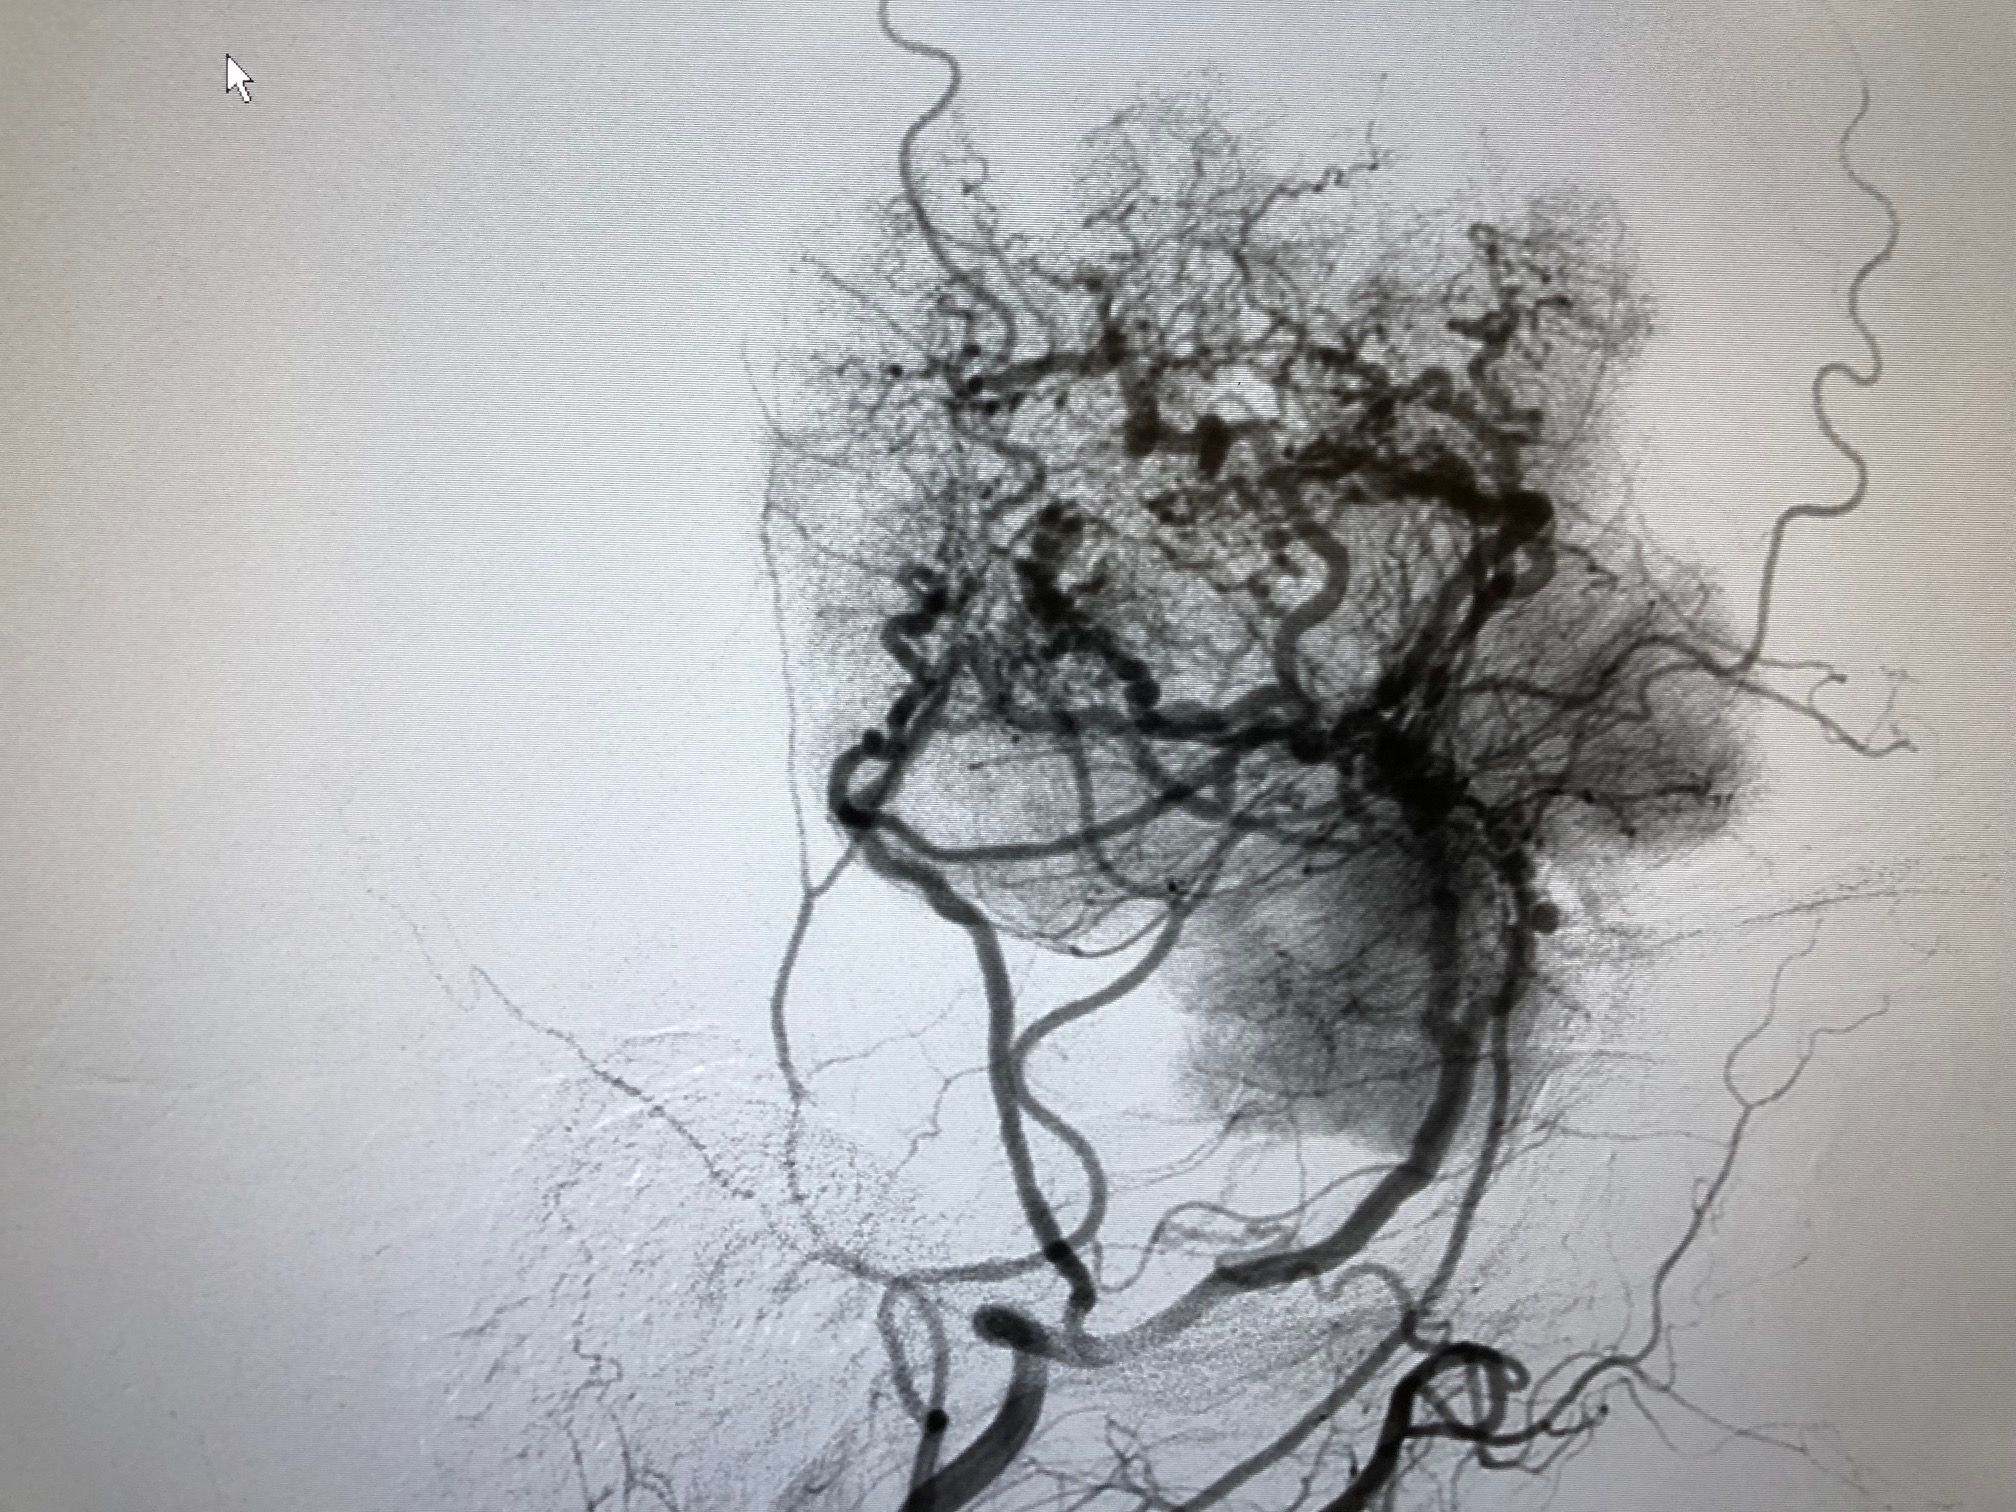

Angiography with preoperative embolization of the meningioma.

Preoperative angiography after embolization of the meningioma.